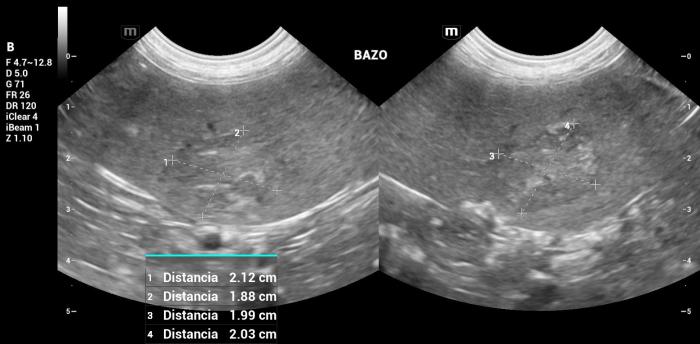

Hallazgos ultrasonográficos (modo B y doppler color): El bazo se encontraba marcadamente agrandado en todos sus ejes, alcanzando la región mesogástrica derecha, con un espesor a nivel del cuerpo de 3.13 cm. Su conformación mostraba plegamiento parcial, compatible con cambios por desplazamiento, aumento de volumen o pérdida de soporte abdominal.

El parénquima conservaba una ecogenicidad homogénea, aunque se identificaron dos lesiones focales:

- Lesión mayor (cuerpo/cola) (Figura 17):

- Ecogenicidad mixta, compuesta por áreas isoecoicas y otras hiperecoicas transónicas (sin evidencia de mineralización).

- Tamaño: 2.12 × 2.03 × 1.99 cm.

- Vascularización Doppler color positiva (Figura 18-19).